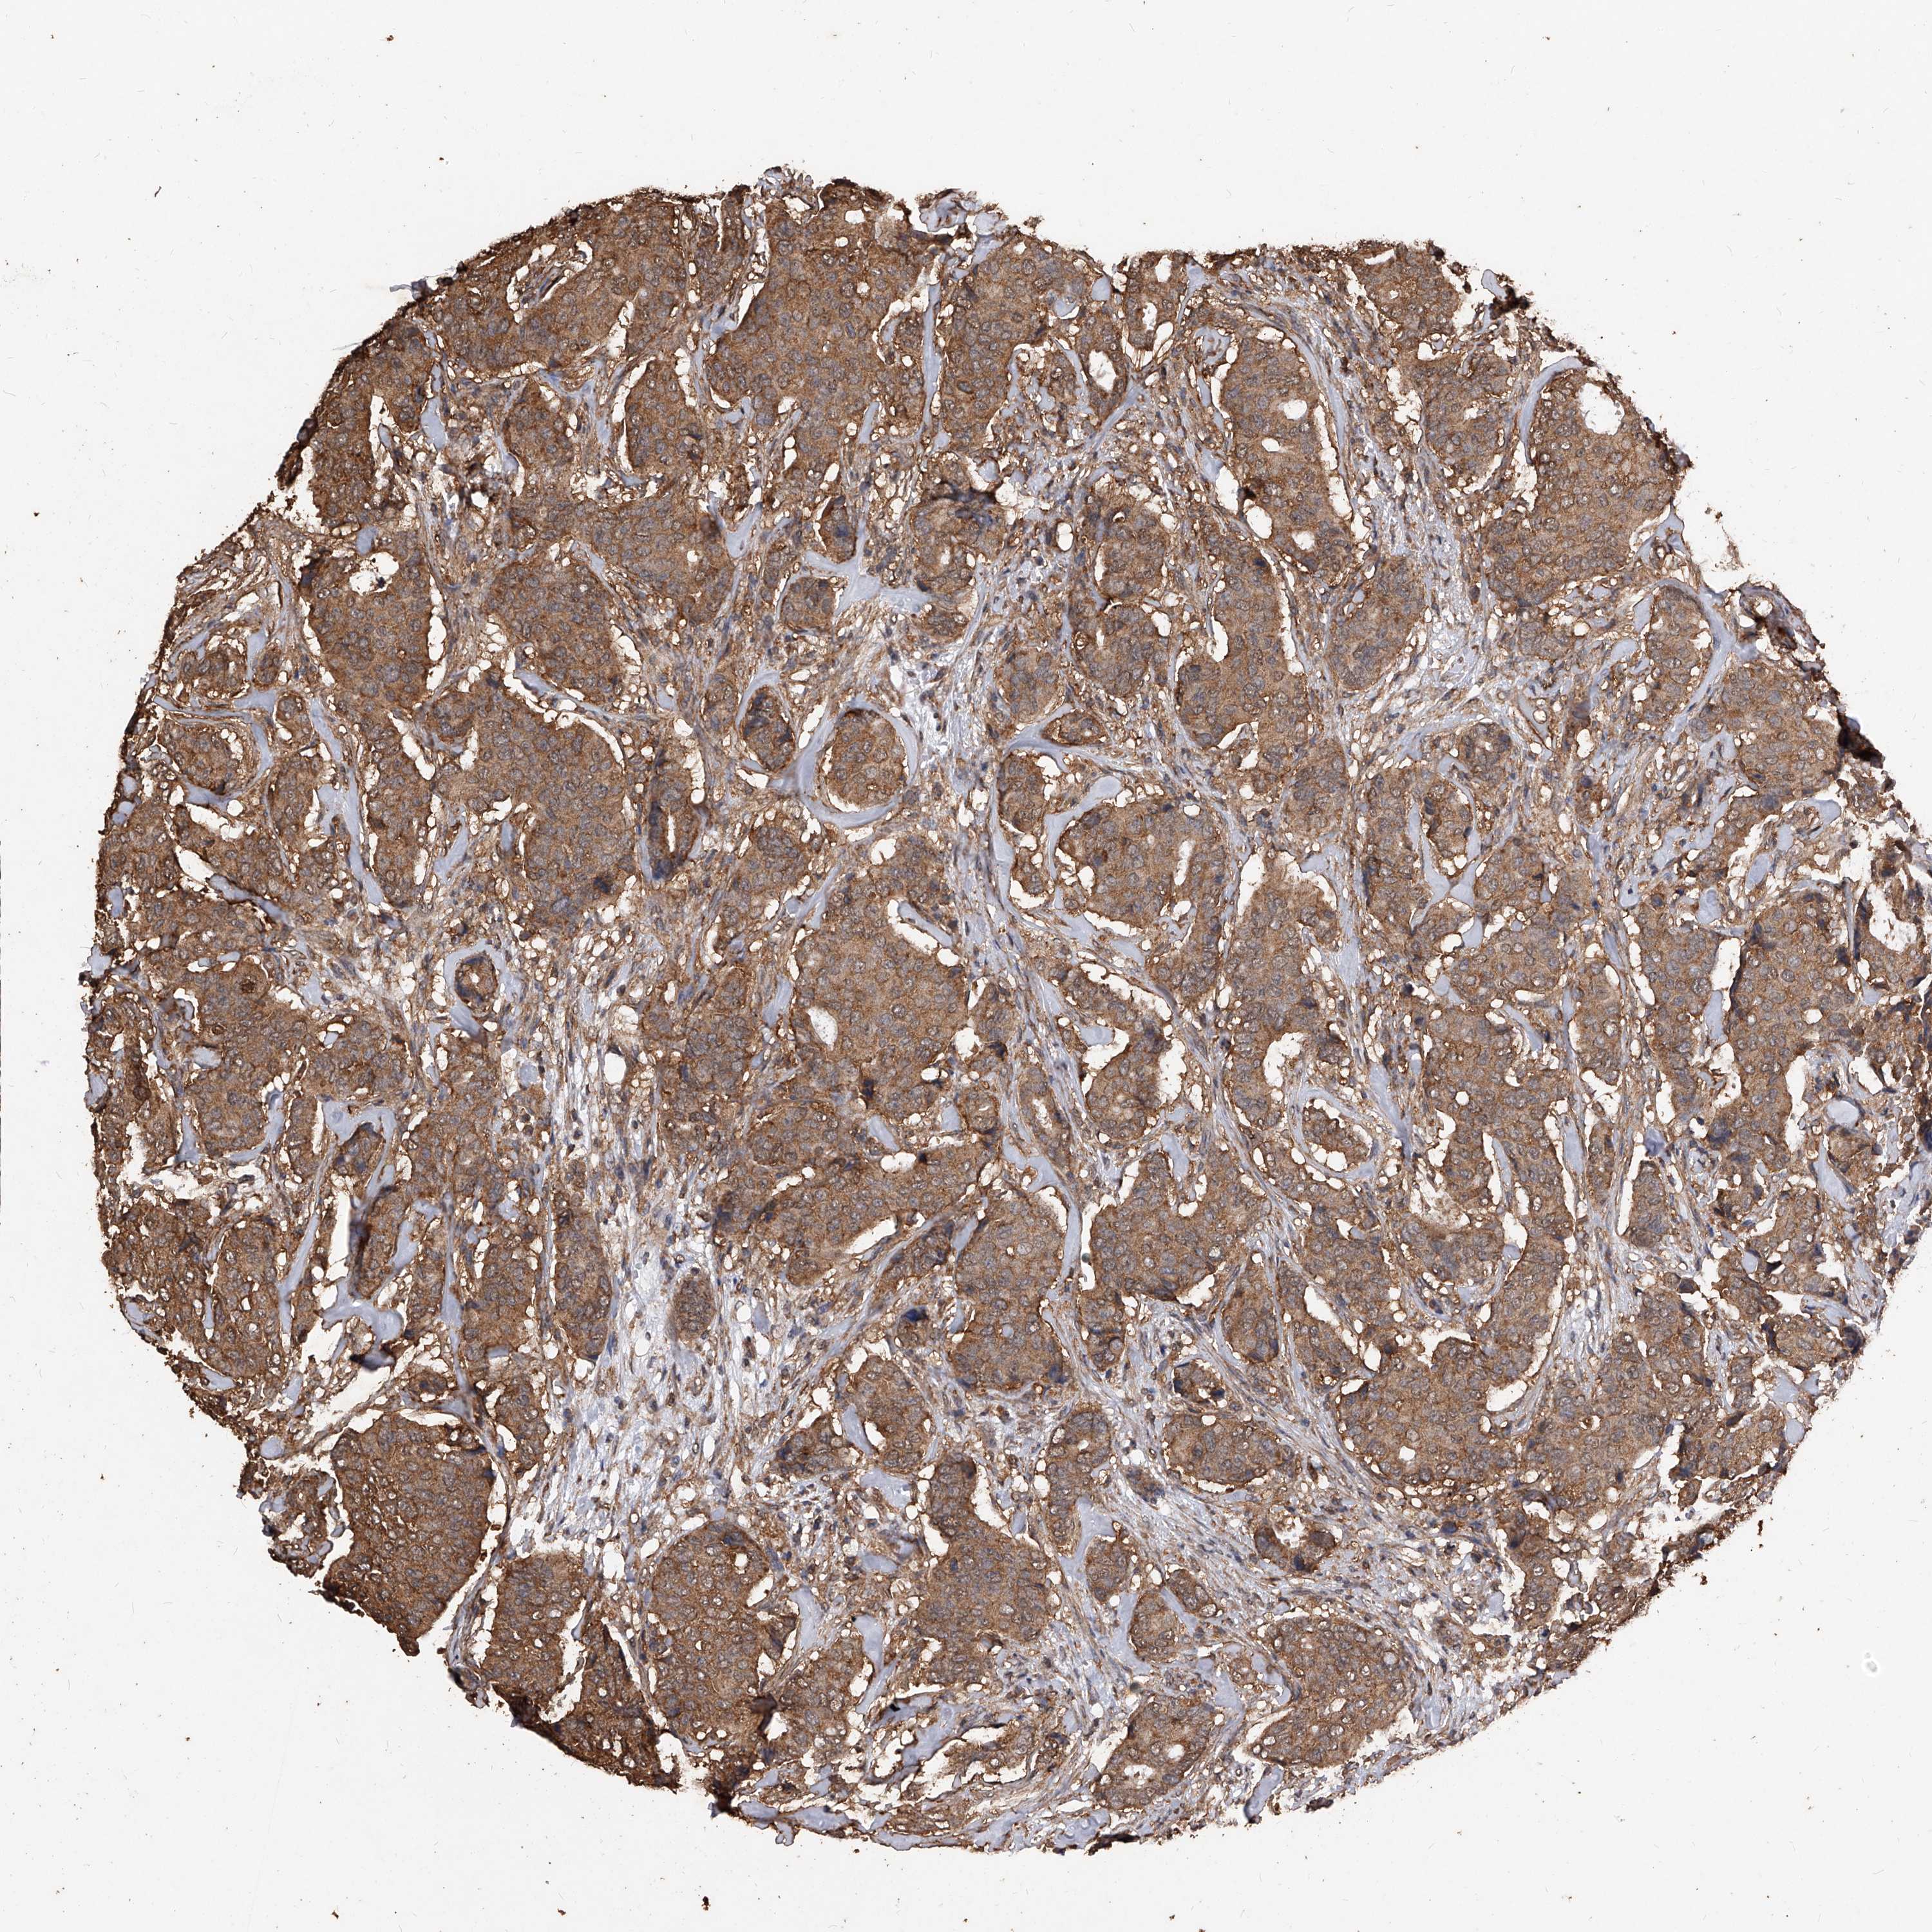

BRCA TCGA BRCA VALIDATION PROTEIN EXPRESSION